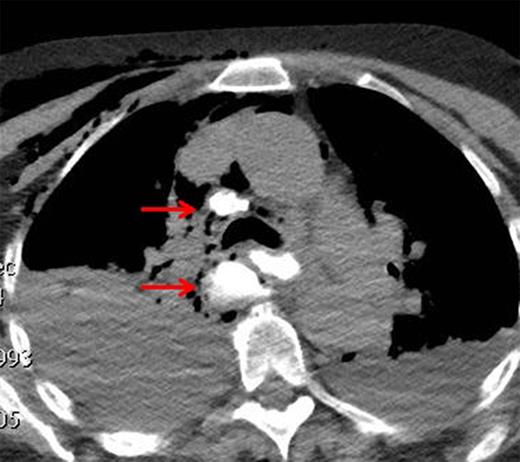

On arrival, she was hemodynamically normal. Pertinent laboratory markers included a white blood cell count of 11, serum bicarbonate of 20 and a lactate of 1.5. A computed tomography (CT) scan of the chest with oral contrast, administered immediately before the study, demonstrated extravasation from the middle third of the esophagus into the right chest and mediastinum with minimal flow distally into the lower esophagus and stomach (Fig. 1). The clinical picture was suggestive of a distal esophageal obstruction from either stricture or neoplasm. Bilateral chest tubes were placed and supportive care initiated, including broad-spectrum antibiotics and fluconazole. An urgent esophagogastroduodenoscopy (EGD) was performed to evaluate for mass or stricture in the distal esophagus, and this showed an obvious perforation with extrusion of fluid and gastric contents noted along the right mid-esophagus with no evidence of stricture or tumor (Fig. 2). The patient was taken to the operating room, and a right posterolateral thoracotomy was performed. Upon entering the chest, murky purulent fluid was noted throughout the right pleural space and mediastinum. Further exploration revealed a transmural perforation in the mid-esophagus, originating at the level of the azygos vein, extending ∼5 cm distally. The right pleural space was debrided and irrigated, and the esophageal tear was repaired primarily after it had been fully exposed. 3-0 Vicryl sutures were placed in an interrupted fashion through the mucosa for the full length of the repair, and this was reinforced with an intercostal muscle flap as the muscular layer of the esophagus was not suitable for repair sutures.

CT demonstrating extravasation of oral contrast into the right chest and mediastinum.